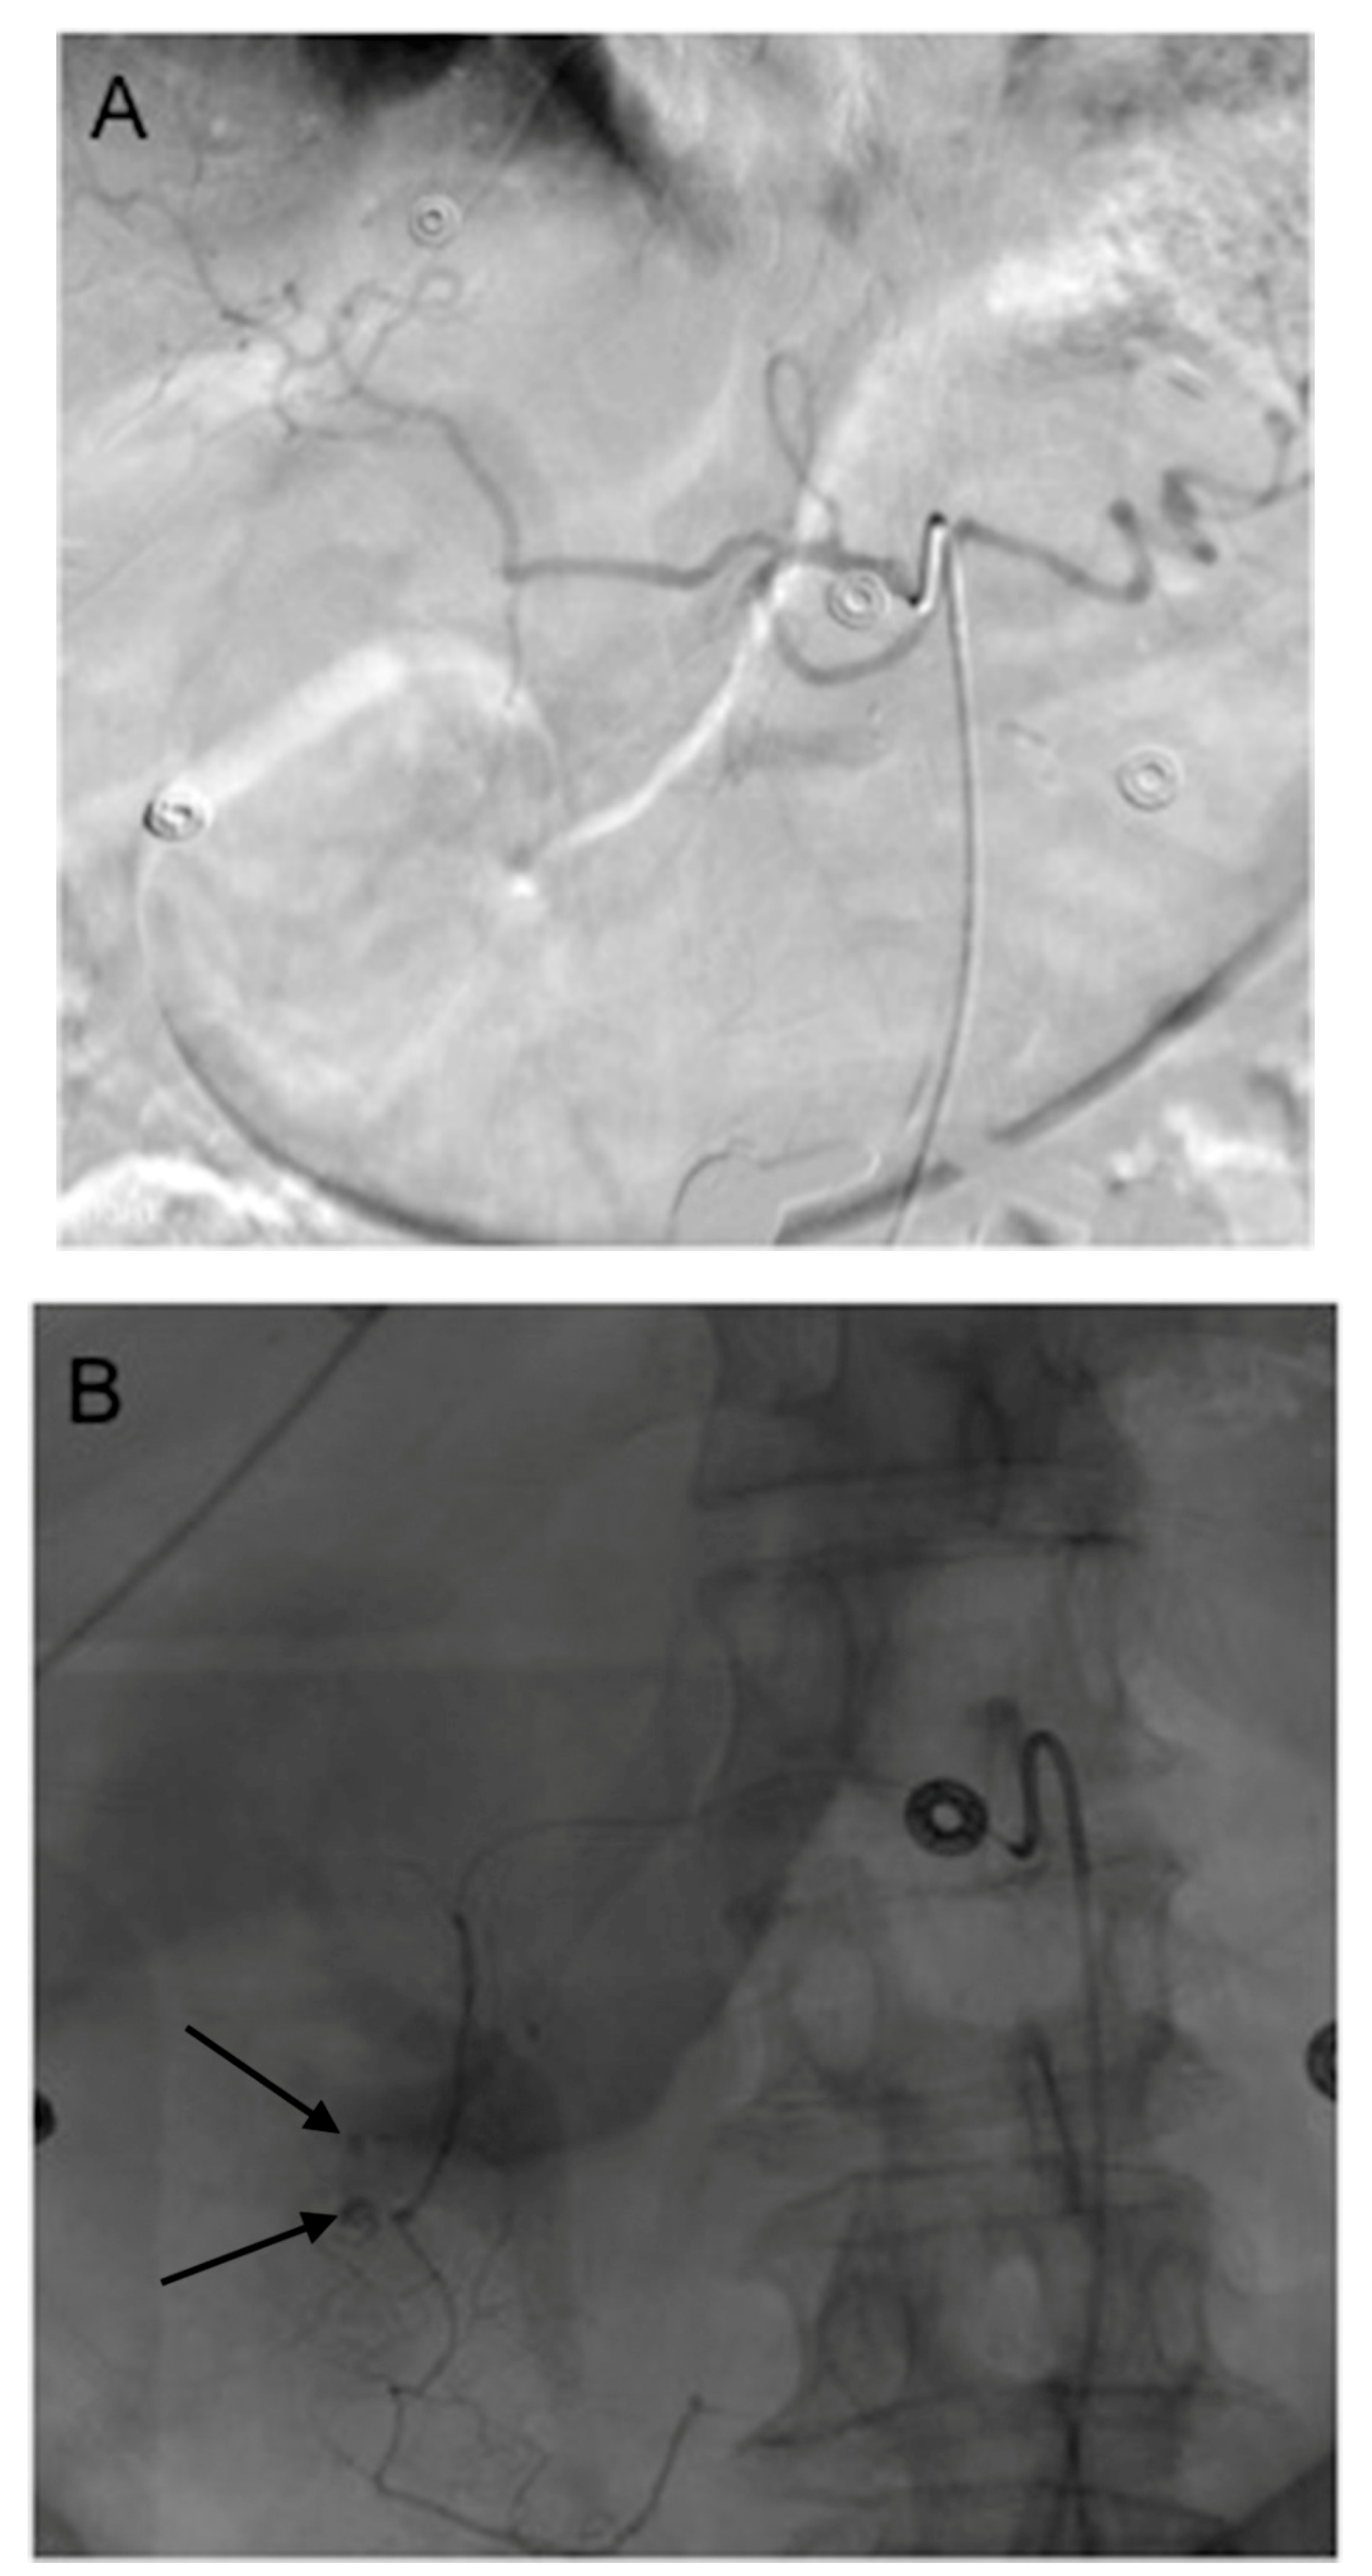

- Schelhorn, J.; Theysohn, J.; Ertle, J.; Schlaak, J.; Mueller, S.; Bockisch, A.; Lauenstein, T. Selective internal radiation therapy of hepatic tumours: Is coiling of the gastroduodenal artery always beneficial? Clin. Radiol. 2014, 69, e216–e222. [Google Scholar] [CrossRef] [PubMed]

- Petroziello, M.F.; McCann, J.W.; Gonsalves, C.F.; Eschelman, D.J.; Anne, P.R.; Sato, T.; Doyle, L.A.; Frangos, A.; Brown, D.B. Side-branch embolization before 90Y radioembolization: Rate of recanalization and new collateral development. Am. J. Roentgenol. 2011, 197, W169–W174. [Google Scholar] [CrossRef] [PubMed]

- Liu, D.M.; Salem, R.; Bui, J.T.; Courtney, A.; Barakat, O.; Sergie, Z.; Atassi, B.; Barrett, K.; Gowland, P.; Oman, B.; et al. Angiographic considerations in patients undergoing liver-directed therapy. J. Vasc. Interv. Radiol. 2005, 16, 911–935. [Google Scholar] [CrossRef] [PubMed]

- Enriquez, J.; Javadi, S.; Murthy, R.; Ensor, J., Jr.; Mahvash, A.; Abdelsalam, M.E.; Madoff, D.C.; Wallace, M.J.; Avritscher, R. Gastroduodenal artery recanalization after transcatheter fibered coil embolization for prevention of hepaticoenteric flow: Incidence and predisposing technical factors in 142 patients. Acta Radiol. 2013, 54, 790–794. [Google Scholar] [CrossRef] [PubMed]